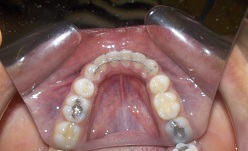

An image of molds below

In this phase Cephalometric X-Rays(above), Panoramic X-Rays(below), Orthodontic Photos(Interoral and Extraoral) and Impression(Molds) are made and taken for study purposes.